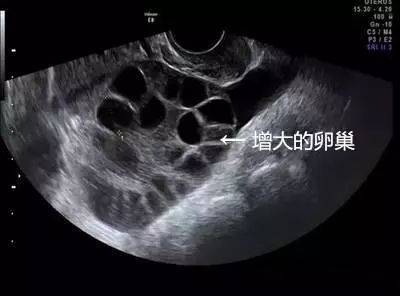

取卵成功后,中介就没有再联系琳琳。但取卵5天后,琳琳出现持续性下腹胀,还有十分明显的胸闷症状。她再次联系卖卵中介,但对方拒绝承担责任,还威胁琳琳不要再纠缠。琳琳到我省这家妇幼保健院就诊,B超提示腹腔内大量积液,胸腔少量积液,卵巢增大超过3倍以上,考虑是卵巢过度刺激综合症,被收治住院。

1、卵巢过度刺激综合征,尤其是瘦小、年轻的女孩子更容易得。卵巢增大导致卵巢壁毛细血管通透性增大,体液积聚于组织间隙,进而使引起腹腔积液、胸腔积液,甚至会导致血栓,危害生命。